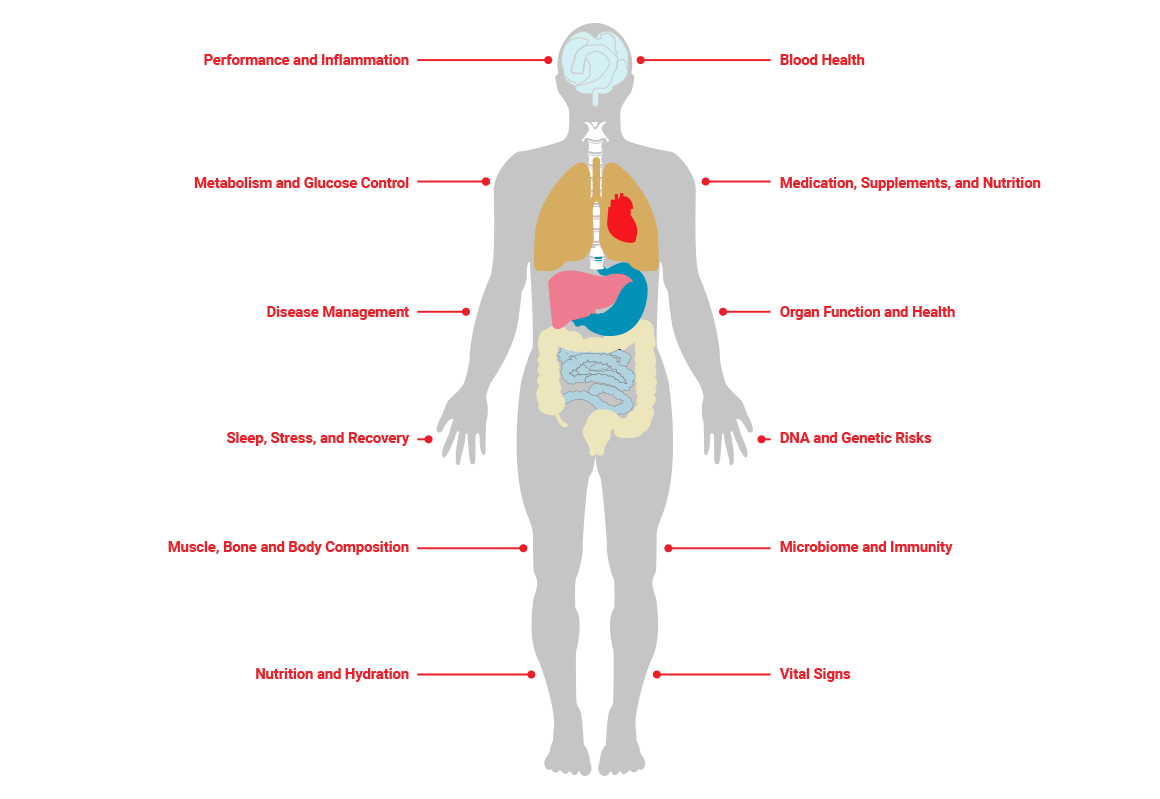

Your body's hidden biomedical ecosystem plays a vital role in your personal fitness journey. When this system lacks harmony, achieving peak fitness and well-being becomes challenging.

We help you see and control your hidden biomedical data alongside your fitness and empower you to better overall health and wellbeing.

We place you into our unique Biomedical Fitness eco system where your healthcare data, tests, and how you feel inside, and outside are constantly monitored.

We place our clients into biomedical fitness healthcare ecosystem, ensuring that your path to success is well-coordinated and managed by our team.